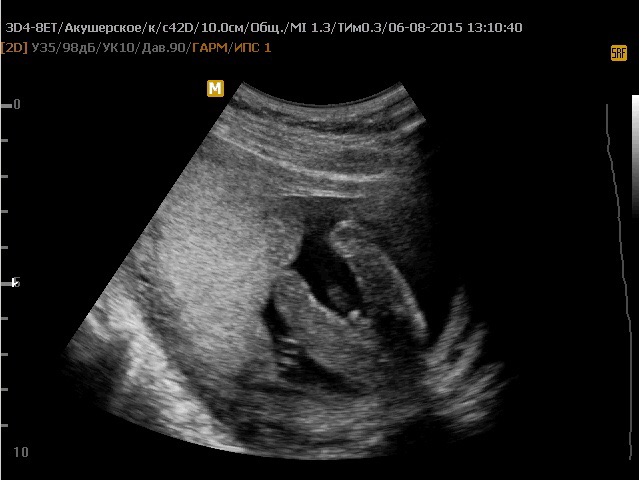

Качество аппаратуры УЗИ также играет важную роль. Современные 3D и 4D аппараты дают более четкую картинку, но они есть не во всех клиниках. Кроме того, немаловажен опыт врача. Как в любой профессии, здесь тоже есть асы и новички. Бывает, что неопытный специалист принимает пуповину за половой член или, наоборот, не может разглядеть его из-за неудачного расположения плода.

- Выбирайте клиники с современным оборудованием. 3D и 4D УЗИ дают более четкую картинку.